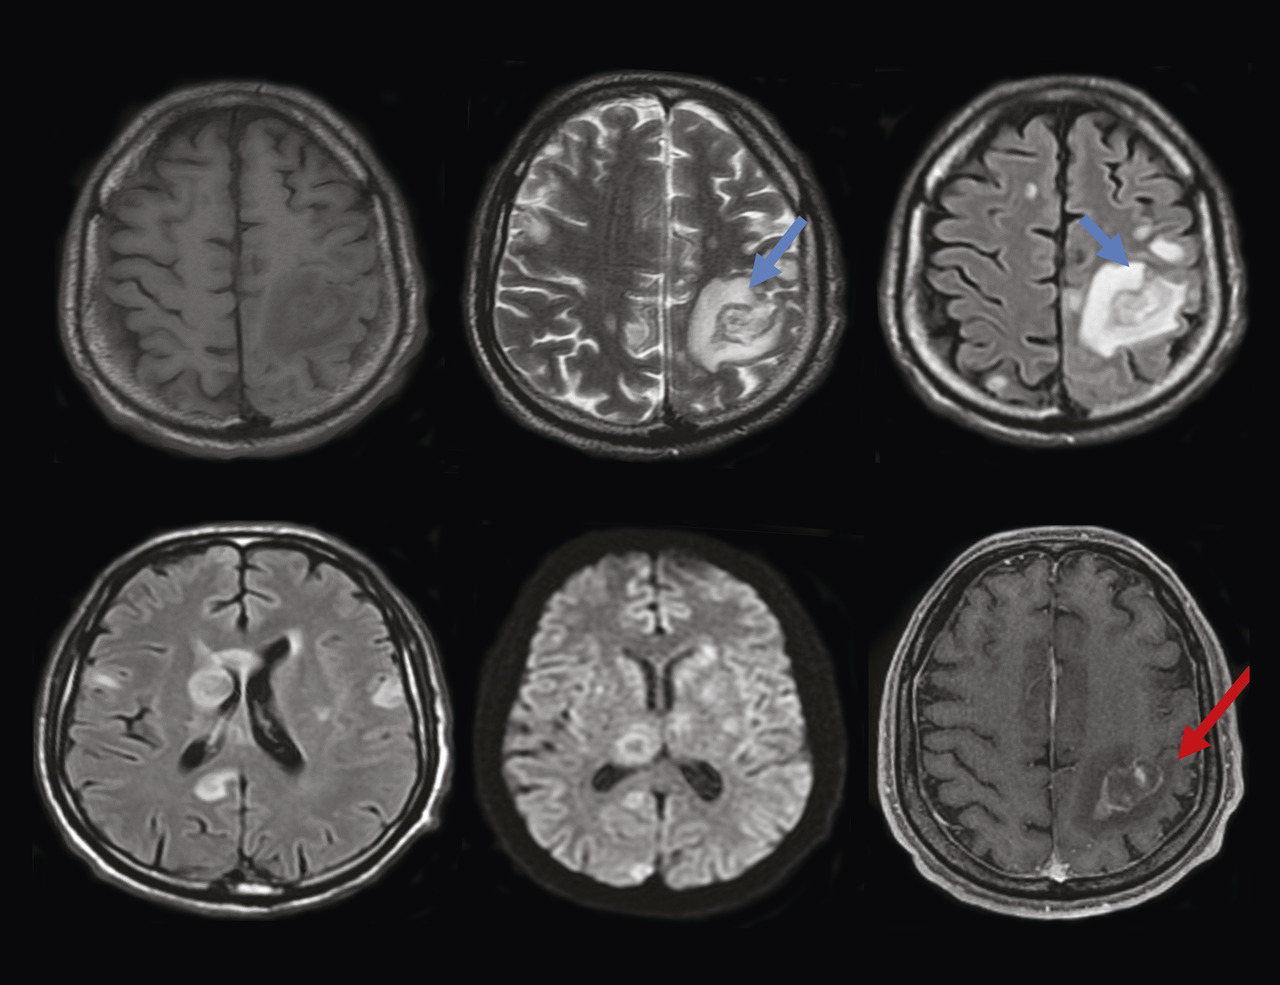

Un homme âgé de 51 ans, sans antécédents particuliers, a depuis deux semaines une hémiplégie droite et une dysarthrie évoluant dans un contexte d’apyrexie et d’altération de l’état général. À l’examen clinique, le patient, conscient, est stable sur le plan hémodynamique et respiratoire ; l’examen neurologique objective un déficit moteur de l’hémicorps droit. Les constantes sont les suivantes : température à 37,3 °C, pression artérielle de 125/75 mmHg, indice de masse corporelle (IMC) de 18,6 kg/m2. Le bilan biologique initial (hémogramme et protéine C-réactive) est normal. Le patient bénéficie en urgence d’une tomodensitométrie (TDM) cérébrale sans et avec injection du produit de contraste montrant des plages hypodenses éparses non systématisées avec prise de contraste annulaire après injection du produit de contraste (fig. 1 ). Par la suite, une imagerie par résonance magnétique (IRM) cérébrale caractérise ces multiples lésions parenchymateuses cérébrales sus- et sous-tentorielles en hypersignal T1, hypersignal T2 hétérogène, en hypersignal et Flair, avec une restriction sur la diffusion, se rehaussant en cible excentrée « target sign », avec œdème périlésionnel (fig. 2 ). Face à cet aspect radiologique, le diagnostic de toxoplasmose cérébrale est évoqué. Puis une sérologie toxoplasmique et au virus de l’immunodéficience humaine (VIH) se révèle positive, avec un taux de CD4 de 89 cellules/mm3. Le patient est traité par un antiparasitaire (pyriméthamine avec acide folinique) associé à une trithérapie antirétrovirale. Malgré une prise en charge rapide, l’évolution est marquée par une aggravation du tableau clinique, avec installation de troubles de la conscience ayant conduit au décès.

La toxoplasmose cérébrale est une infection parasitaire du système nerveux central par un protozoaire nommé Toxoplasma gondii. Cette infection concerne les patients immunodéprimés, notamment ceux infectés par le VIH.1 La toxoplasmose peut d’ailleurs être révélatrice de cette infection.2 Le tableau clinique est variable ; tout signe neurologique chez un patient atteint du VIH doit donc faire suspecter une toxoplasmose cérébrale.2 L’imagerie en coupe (TDM et IRM) joue un rôle important dans la démarche diagnostique en montrant classiquement des lésions multifocales de localisation variable, réalisant un effet de masse sur le parenchyme cérébral. Après injection, les lésions se rehaussent en périphérie en prenant parfois un aspect classique de « cible excentrée ».3 L’effet de masse peut entraîner un engagement sous-falcoriel en cas de lésions hémisphériques ou une hydrocéphalie obstructive.3 La confirmation du diagnostic est biologique.2 Le traitement est anti-infectieux, visant Toxoplasma gondii et le VIH, et symptomatique contre l’hypertension intracrânienne.1 Le traitement antiparasitaire est généralement fondé sur la pyriméthamine en association avec un médicament d’appoint comme la sulfadiazine ou la clindamycine ; l’acide folinique est prescrit en même temps que la pyriméthamine, pour prévenir les carences en folates. Chez les patients atteints du syndrome d’immunodéficience acquise (sida), le traitement de la toxoplasmose cérébrale doit être associé à une thérapie antirétrovirale efficace pour contrôler la charge virale et restaurer la fonction immunitaire.1 Le traitement de l’entourage n’est pas nécessaire. Il est recommandé de tester les partenaires sexuels des personnes vivant avec le VIH pour prévenir la transmission du virus.